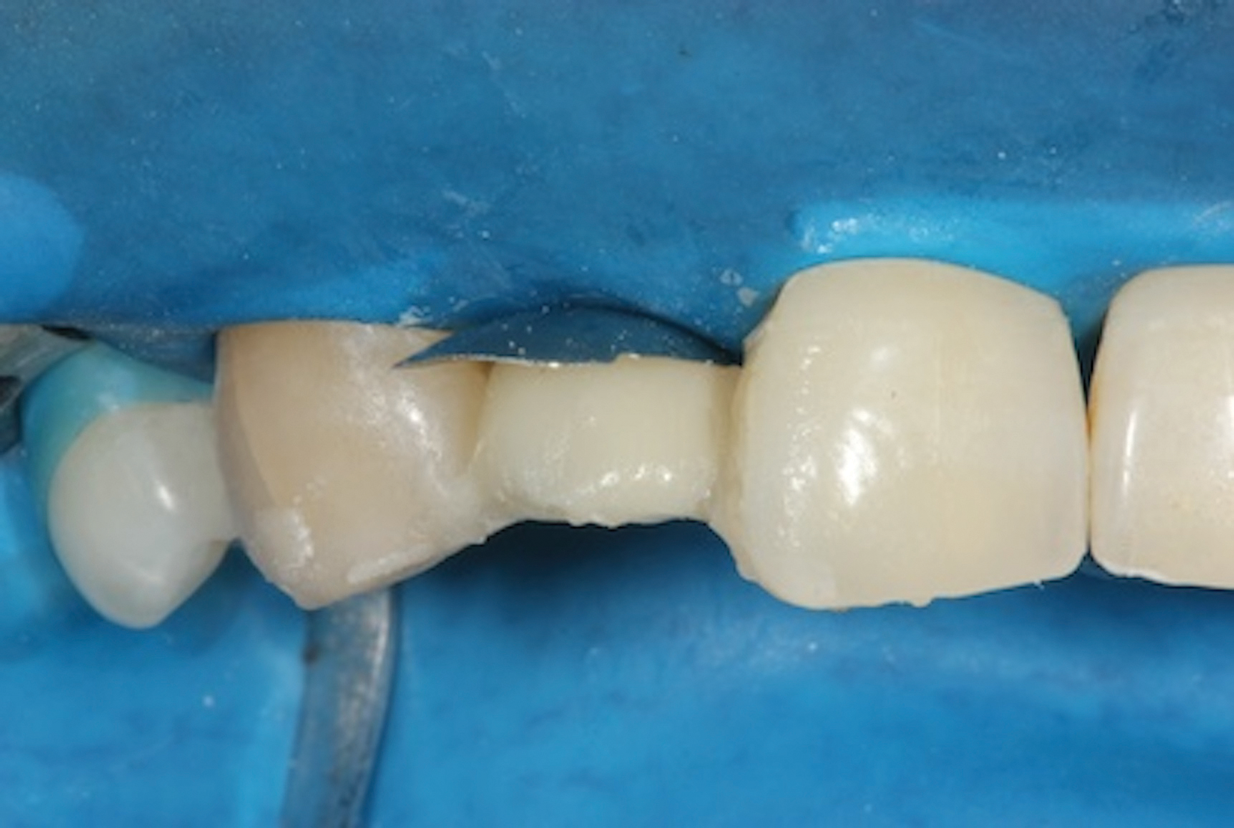

(3.) Placement of a rubber dam to achieve isolation.

Figure 3

1. Isolate the Operating Field

For any adhesive procedure, optimizing bond strength hinges on achieving proper isolation of the operating field. Placing a rubber dam ensures a pristine and fluid-free field, creating an ideal environment for both bonding and the subsequent development of the resin bridge (Figure 3). Achieving complete isolation is particularly important in cases involving replacement of a missing tooth immediately after extraction or implant placement.